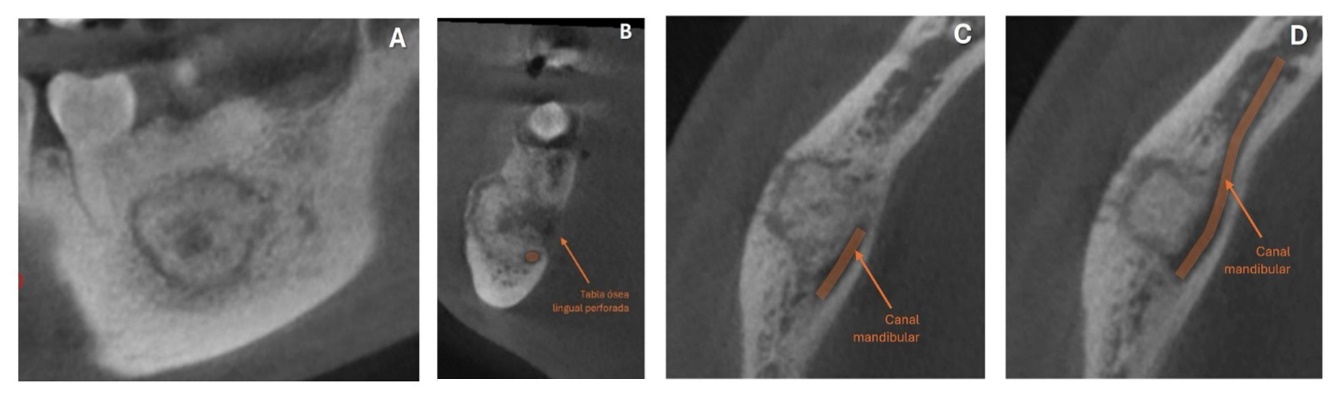

Se presenta en la Facultad de Odontología paciente masculino de 19 años con aumento de volumen y dolor agudo de 3 meses de evolución. A la evaluación clínica se observa ensanchamiento de la tabla ósea vestibular de consistencia petrosa. La Tomografía Computarizada de Haz Cónico muestra una lesión relacionada al diente 4,6, además, se realizó una biopsia incisional inicial (Figura 1).

Figura 1. En el corte radiográfico sagital (A) se observa una zona de densidad mixta rodeada por un halo hipodenso en relación con la raíz distal del 4,6. En el corte radiográfico coronal (B) la tabla ósea lingual se encuentra perforada. Los cortes radiográficos sagitales (C, D) muestran la relación de la lesión con el canal mandibular. El corte histológico (E) muestra islotes de cemento dental. Estos hallazgos indican el diagnóstico de cementoblastoma.